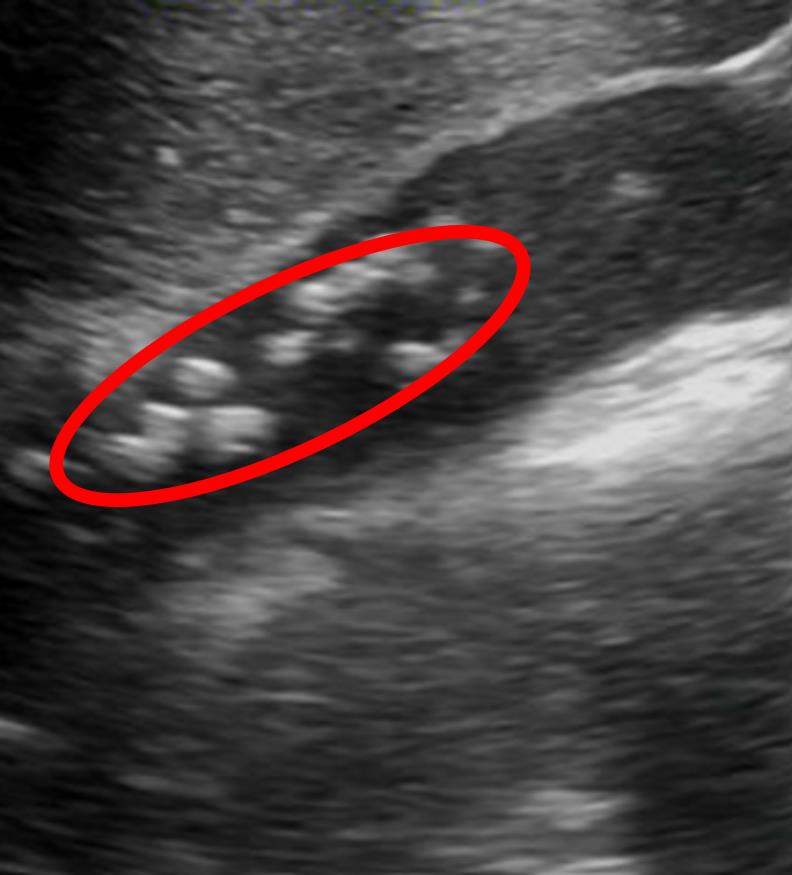

A right upper quadrant ultrasound is obtained and the results are shown in Figure A. Which of the following is her most likely underlying diagnosis?

Figure/Illustration A is an ultrasound of the gallbladder demonstrating gallstones (red circle). These findings are consistent with a diagnosis of cholecystitis.